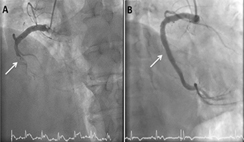

2. 心導管檢查與支架治療:這是當前主流的治療,心導管檢查會從手腕的橈動脈或是鼠蹊部的股動脈打針,先放一個2mm左右的鞘管,接著診斷導管會從這個鞘管順著血流到心臟的冠狀動脈攝影,可以清楚看到血管阻塞(圖A),接著醫師會利用治療導管,讓導線通過病灶,接著順著導線進行氣球擴張與放置支架,讓阻塞的血流得以暢通(圖B)。因為傷口很小,只有傷口處局部麻醉,病人全程清醒,而且比血酸溶解劑的通暢率要高上許多等優點,是目前治療上的首選。國際上目標希望可以儘快在到急診的90分鐘內打通血管,本院心臟團隊的成績也相當優異。

圖A箭頭處:ST段上升心肌梗塞,血管完全阻塞

圖B箭頭處:經過心導管支架置療後血流恢復通暢